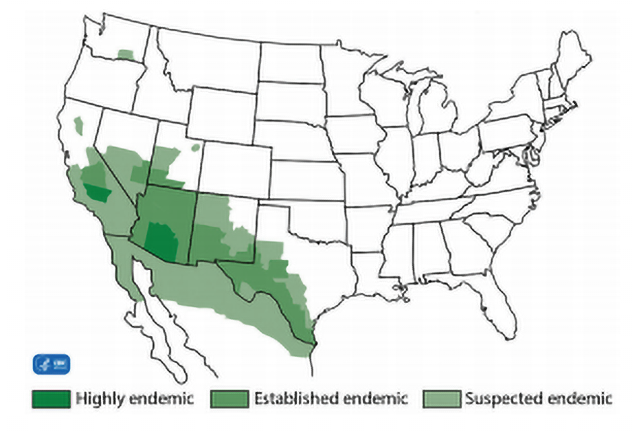

Also known, as "Valley Fever", this fungal infection is endemic to the regions shown below:

What is coccidioidomycosis?